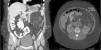

The initial immunosuppression was triple therapy with calcineurin inhibitors (cyclosporine), antiproliferative agents (mofetil mycophenolate) and steroids. Six months later, the immunosuppression regimen was modified by substituting mofetil mycophenolate with everolimus with the two-fold objective of controlling the mild post-transplantation renal dysfunction and assessing the response of the angiomyolipoma to the pharmacological treatment. The dosage of the immunosuppressants was individualized in order to reach plasma levels close to 5ng/ml of everolimus and 100ng/ml of cyclosporine. During follow-up, the renal and pulmonary function remained stable, at stage 0 of bronchiolitis obliterans syndrome. After 6 months of treatment with everolimus, a new abdominal CT demonstrated, after reconstruction, a significant reduction in the size of the renal angiomyolipoma (Fig. 2).